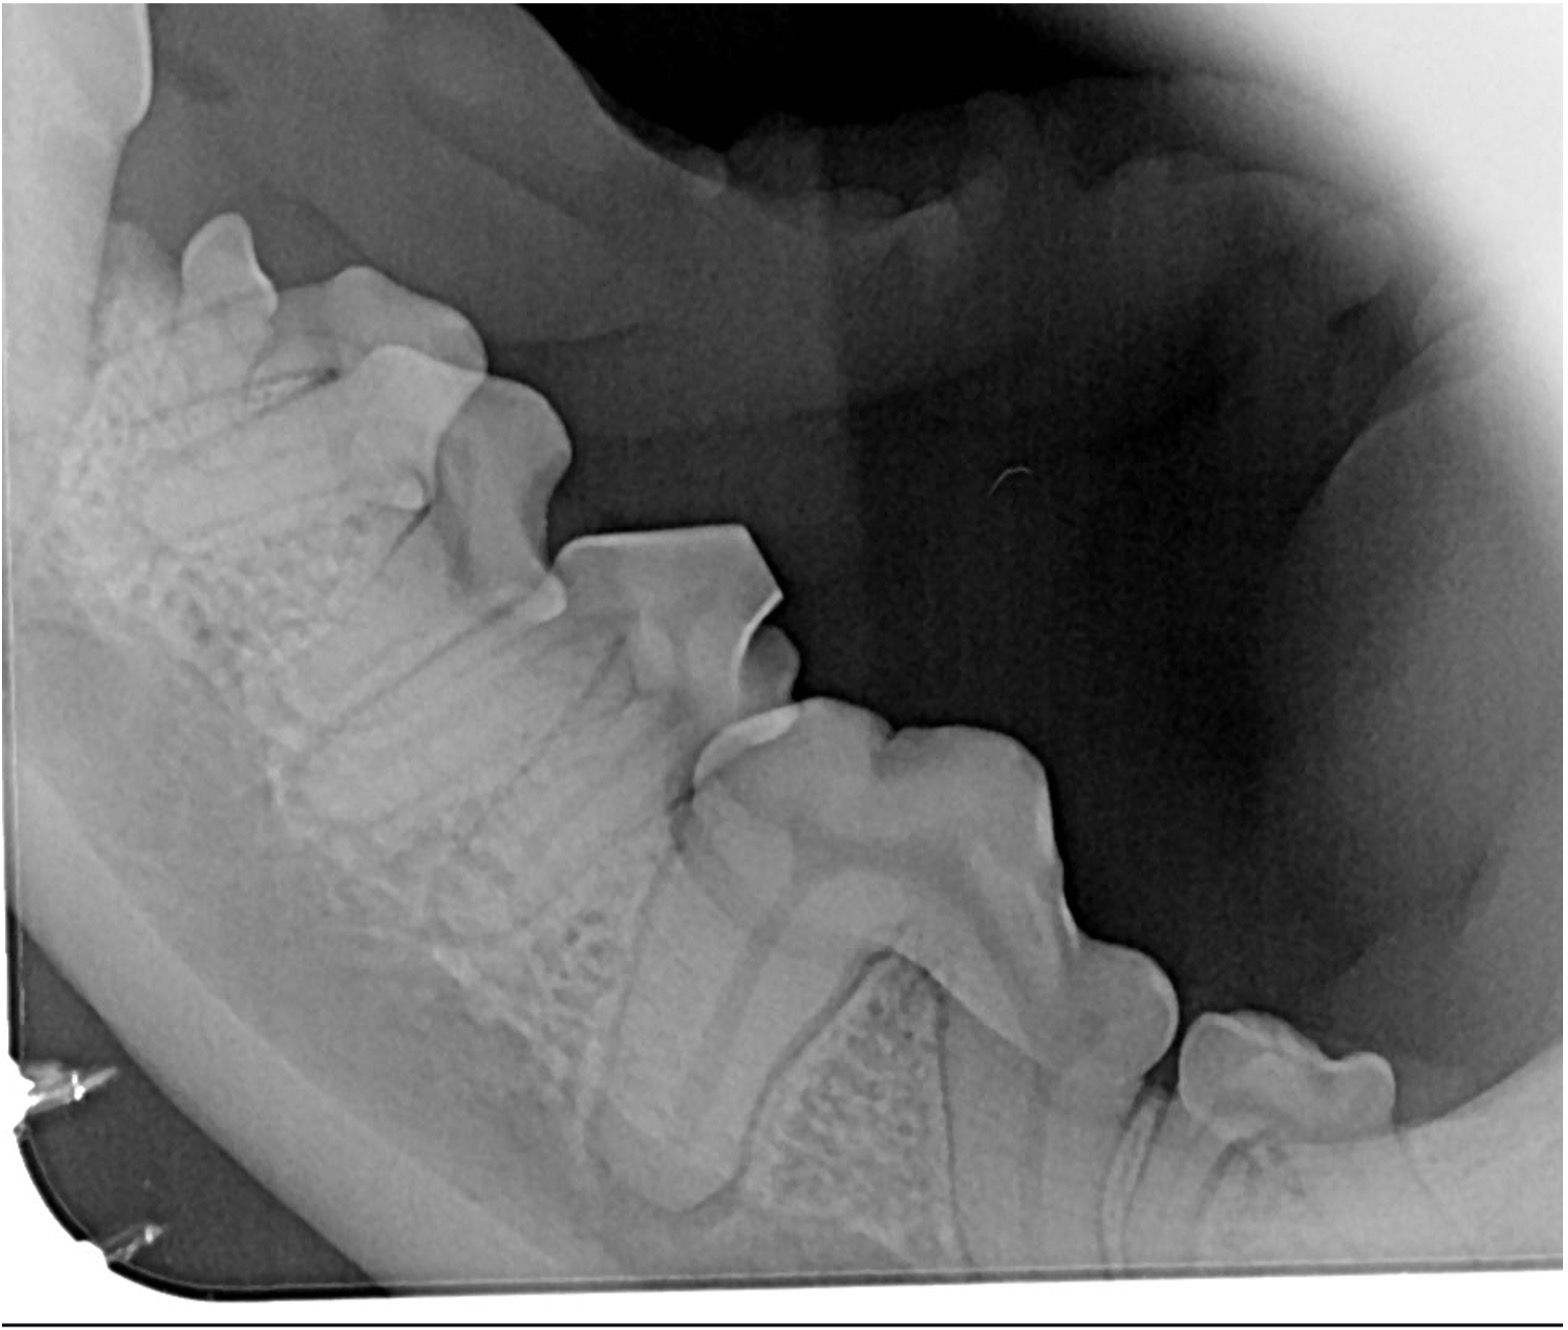

Routine spay or neuter exams offer a prime opportunity for oral health assessments, allowing early intervention for dental abnormalities. The team will assess crowding of teeth (Figure 5) that may allow PD to occur at a faster rate and visualize missing, fractured, displaced teeth causing trauma, and persistent deciduous teeth. This is a perfect time to advocate for baseline dental radiographs (Figure 6) and oral thiol tests to see what is happening under the gum line and decide when their first PRO may be needed.

• Brachiocephalic canines: Dogs with brachiocephalic skull shapes experience crowding and rotated teeth, leading to advanced PD. Additionally, unerupted teeth (Figure 8) in these breeds may result in dentigerous cysts if left untreated.